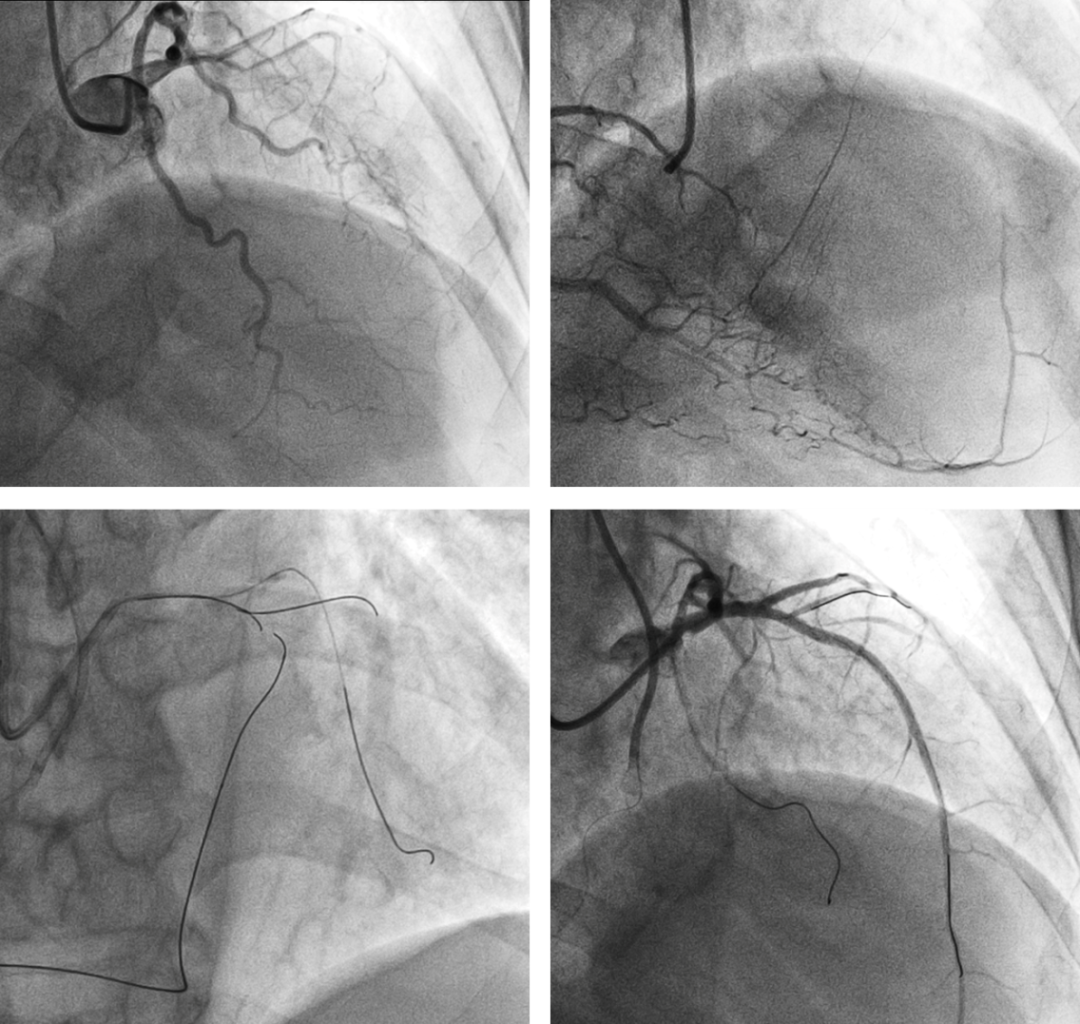

近日,我院心内科“正逆夹击”,以高超的导丝技术成功完成一例高危复杂冠状动脉完全闭塞病变(CTO)手术。 患者胡师傅(化名)68岁,因“反复胸闷10余年,加重一月”入院治疗。 胡师傅约12年前在当地医院诊断为急性心肌梗死,药物保守治疗后出院,之后反复出现胸闷气喘。此次因反复胸闷来我院就诊,入院完善心电图和超声心动图检查,考虑陈旧性心肌梗死,且心脏明显扩大,LV65mm,EF28%,判断已发展为缺血性心肌病,有发生急性左心衰和猝死的风险,病情危重。 心内科副主任鞠成伟和主任医师漆军华详细分析患者病情,考虑冠脉慢性完全闭塞可能,且左前降支病变,需要开通闭塞血管,同时加强药物治疗。 当日行冠脉造影后检查证实了术前判断,患者左前降支中段完全闭塞,血流TIMI 0级,同时合并左回旋支和右冠病变,右冠至左前降支有侧支循环。 鞠成伟主任带领漆军华主任医师,凭借丰富经验,分别穿刺左右桡动脉,在前向导丝通过发生困难后立即启动逆向策略,在微导管支撑下,巧妙的通过右冠状动脉的侧支循环把导丝送至左前降支,经过3个小时40分钟的努力,“左右开弓,穿针引线”,正向和逆向导丝成功会师,终于通过闭塞病变,成功完成PCI。患者闭塞12年的冠脉终于畅通了,心肌供血即刻改善,术后症状较前明显好转。 据鞠成伟主任介绍,冠状CTO病变是指正向TIMI血流0级且闭塞时间≥3个月的冠状动脉阻塞性病变,闭塞时间越长,开通的机会越小。虽然冠脉介入技术不断进展,CTO病变仍被认为是冠脉介入领域难以攻克的“最后堡垒”。开通CTO病变需要手术医师具备丰富的介入经验,熟练掌握各种器械和导丝,而逆向策略是重要的介入技术,增加了手术的成功率。 此例患者伴随血管迂曲、钙化等情况导致介入治疗成功率降低,一旦介入失败,再次介入治疗难度会增加。所幸,患者闭塞12年的冠脉在鞠成伟主任和漆军华主任医师的操作下一次手术即开通。 本例手术的顺利完成,也标志着我院心内科处理冠脉复杂病变的介入技术已经成熟,且达到了新的高度。